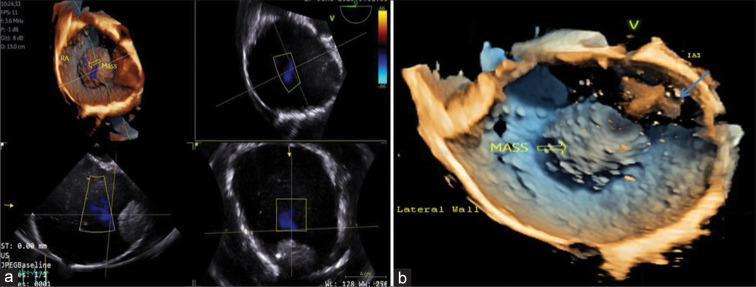

Cardiac masses are a significant cause of patient morbidity and mortality by virtue of their symptoms and surgical removal. Preoperative diagnosis of a cardiac mass is usually based on clinical correlation and transthoracic echocardiography findings. Myxomas are the most common benign cardiac tumors, commonly occurring in the left atrium attached to the interatrial septum near the fossa ovalis. Although, at times atypical location and unusual morphology may pose a diagnostic dilemma with 2D echocardiography. 3D echocardiography with its multifaceted advantages, including multiplanar cropping abilities and superior imaging quality can help distinguish between a clot and a myxoma.